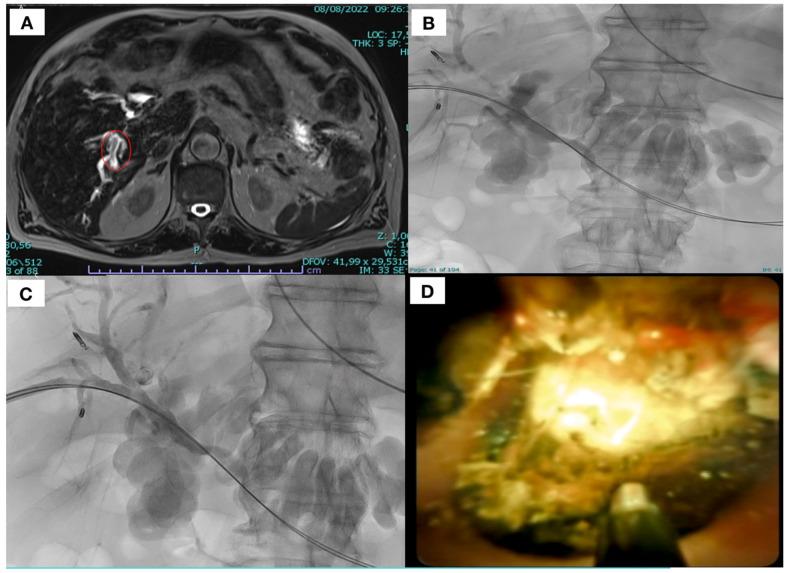

使用SpyGlass DSTM胆道镜经皮肝穿刺碎石术治疗复杂性结石的疗效与安全性

Efficacy and Safety of Percutaneous Transhepatic Lithotripsy Using SpyGlassDSTM Cholangioscopy for the Treatment of Difficult Stones.

本研究的目的是评估使用SpyGlassDSTM胆管镜系统经皮经肝胆道碎石术治疗难取性结石的安全性和有效性。回顾性分析所有使用SpyGlassDSTM胆管镜系统经皮经肝胆道碎石术治疗的患者。作为主要观察指标,评估以下数据:肝胆疾病既往史、结石位置、选择该手术的原因、既往球囊胆管成形术、术前影像学类型、手术时间、技术成功率、临床成功率以及术后并发症(根据CIRSE分类)。单次治疗取得的临床成功被视为“一次成功”,随访期间需要多次治疗则为“二次成功”。10例患者(6例男性,4例女性,平均年龄 = 64岁,标准差 = 22),均因胆结石并发胆管炎,接受了11次使用SpyGlassDSTM的经皮经肝胆道碎石术。所有患者均取得技术和临床成功(100%)。4/10(40%)例患者观察到一次成功,其余6/10(60%)例患者接受再次治疗,均显示二次成功(100%)。未观察到围手术期并发症。11例手术中有10例(90%)在随访的前30天内未记录到相关不良事件。1/11例(9%)在术后数天(<30天)记录到轻度并发症(根据CIRSE分类为I级)。总之,使用SpyGlassDSTM胆管镜经皮经肝胆道碎石术治疗难取性结石已被证明是一种安全有效的治疗方法。